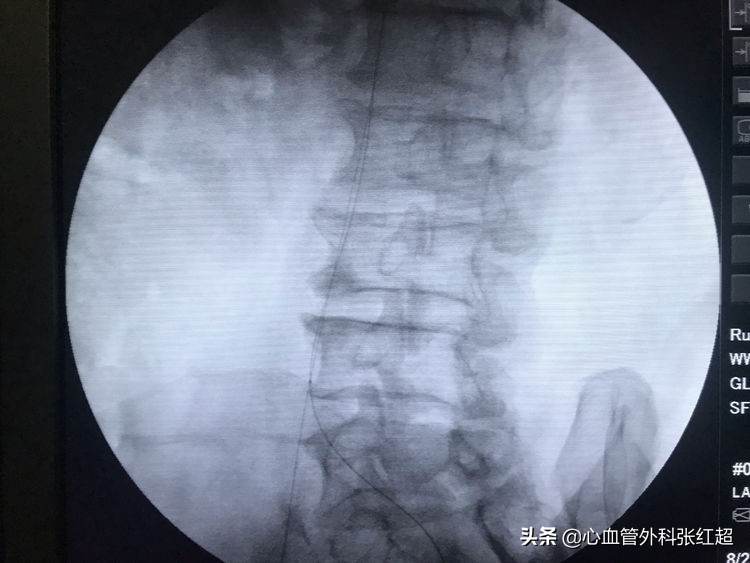

血管造影剂排空快,对侧显影淡,说明血管内血流速度快。

屈曲部稍有残余狭窄。不用硬扩,支架可以在术后贯性序扩。

放两枚支架更容易保证远端释放到位

术后足背、胫后动脉搏动均恢复。